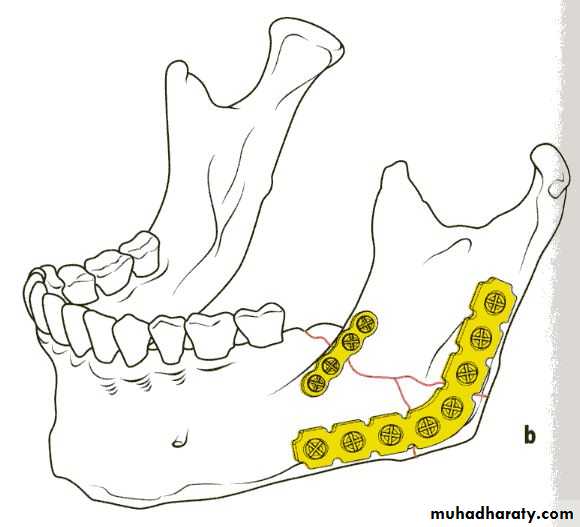

• Rigid internal fixation (plating) these method use bone plates, bone screws or both to fix the fracture.

Plating

If teeth are present IMF is done ; then incision is made and bone is reached either extra orally or intra orally.

The fractured ends are approximated and screw holes are made such that at least 2 screws can be placed on either side of the fracture.

The champy,s technique of plate fixation

1- Use mono cortical screw fixation ; place a minimum of 2 screws on each side of the fracture.2- The more posterior the fracture the more higher the plate should be placed . The more anterior the fracture , the closer the plate should be placed to the lower border.

3-To avoid devitalization of bone , place plates supra periosteally in atrophic edentulous mandible and extensively comminuted fracture.

In plating posterior mandible single upper border plate is enough for fixation. While in plating anterior mandible , two plates are required to help counter the torsional forces of fracture in this location.